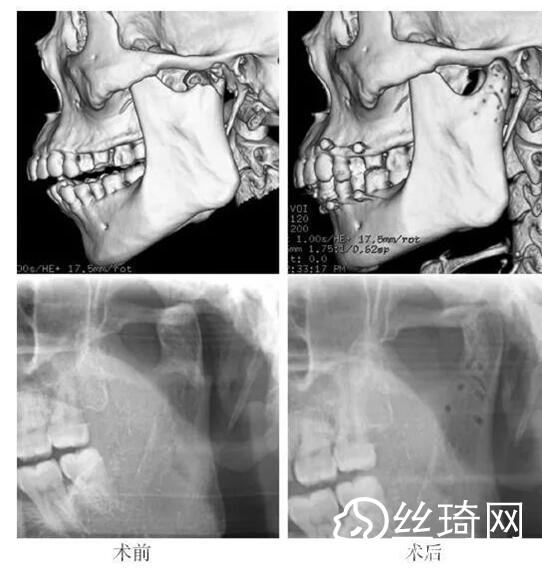

在106側(cè)中,髁突高位矢狀骨折46側(cè),中位髁頸骨折26側(cè),低位髁頸下骨折34側(cè)。髁突高位矢狀骨折及中位髁頸骨折均經(jīng)耳屏前徑路復(fù)位;34側(cè)低位髁頸下骨折中,經(jīng)耳屏前徑路復(fù)位13側(cè),頜下徑路復(fù)位19側(cè),頜后徑路復(fù)位1側(cè),穿腮腺徑路復(fù)位1側(cè)。髁突高位矢狀骨折復(fù)位后以1~2枚可吸收長螺釘固定(圖1)[3],采用的可吸收內(nèi)固定系統(tǒng)為BioSorb(ConMed Linvatec,芬蘭)、Inion OTPS(Inion,芬蘭);規(guī)格:直徑2 mm,長度15~20 mm。中位髁頸骨折及低位髁頸下骨折多以2塊可吸收板固定(圖2)[3],個別病例以1塊或3塊可吸收板固定,采用的可吸收內(nèi)固定系統(tǒng)為BioSorb(ConMed Linvatec,芬蘭)、Grand Fix(Gunze,日本)、Inion OTPS(Inion,芬蘭);規(guī)格:直4孔板,孔徑 mm或2.5 mm,長度21~35 mm,螺釘直徑 mm或2.5 mm,長度7~10 mm??晌蔗敯宓氖中g(shù)操作采用專用器械工具盒,并遵照廠家操作指引進(jìn)行。

82例髁突骨折患者,術(shù)后隨訪6個月至3年,平均年。所有患者術(shù)后未訴明X不適,面型基本對稱,面部肌肉運(yùn)動正常,咬合對位良好,開口度~4.2 cm,平均(±)cm。3例患者開口型輕度偏斜,均為髁突高位骨折,其中2例為粉碎性骨折行骨折碎片摘除,1例為矢狀骨折,以可吸收螺釘固定后,創(chuàng)口感染,隨后行局部清創(chuàng)并取出髁突骨折片及可吸收螺釘,創(chuàng)口愈合良好。96側(cè)髁突骨折中,2例髁頸下骨折術(shù)后復(fù)查CT顯示輕度移位,但患者無功能障礙,持續(xù)觀察,未做特殊處理。其他患者未見明X排斥反應(yīng)及并發(fā)癥。